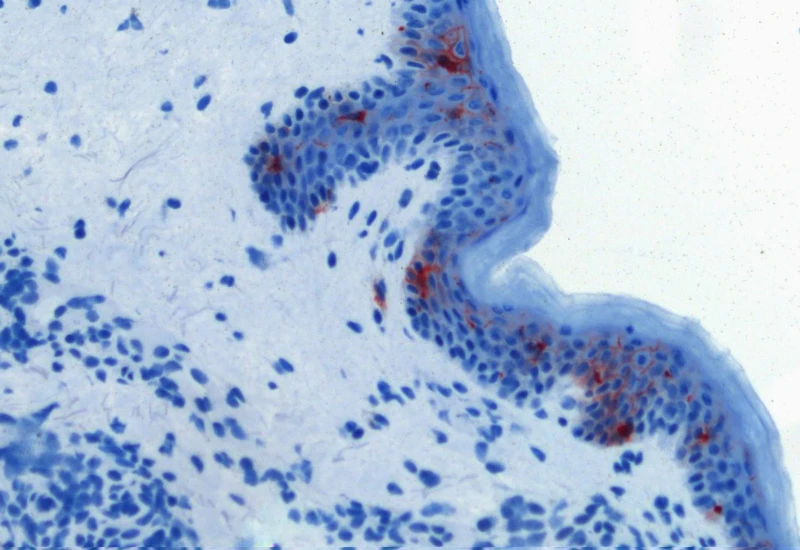

IHC Macrophages

Detect macrophages in IHC samples, apply area and distance-range algorithms to measure Langerhans cell distances to the epidermis border inside/outside, and export up to 20 parameters per cell compartment plus boundary distance.

The IHC Macrophages App detects macrophages based on adequately stained IHC samples (e.g. CD68). The App further proves area detection and distance range algorithms to determine the distance of Langerhans cells from the border of the epidermis within and without. Each segmented cell compartment is measured for up to 20 parameters, as is the distance of each cell to the boundary.

Original image